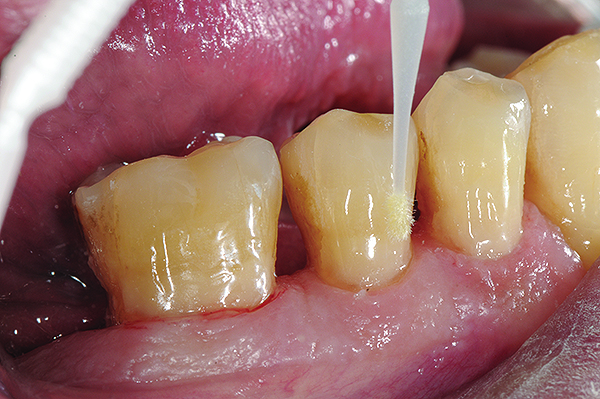

Fig 8. Cavities were bulk-filled with high-viscosity auto-curing GIC.

Figure 8

Fig 9 and Fig 10. After GIC was manually condensed and shaped, a nanofilled resin glaze was liberally applied to the surface of the finished restoration (Fig 9) and light-cured (Fig 10).

Figure 9

Figure 10